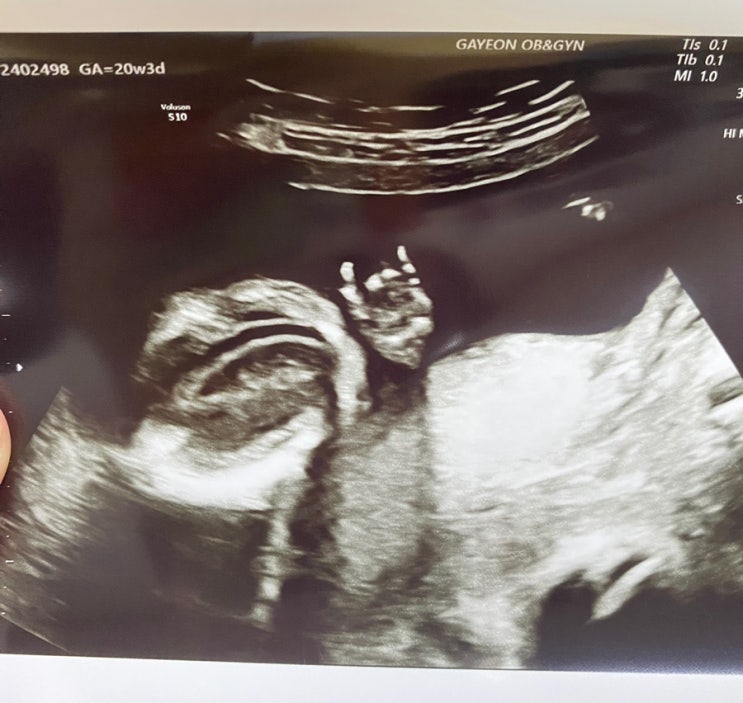

[임신20주] 2차 정밀 초음파.

24년 8월 23일 2차 정밀 초음파 예약 날. 당연히 아무 이상 없을 거라 생각하지만 그래도 불안한 마음은 어...